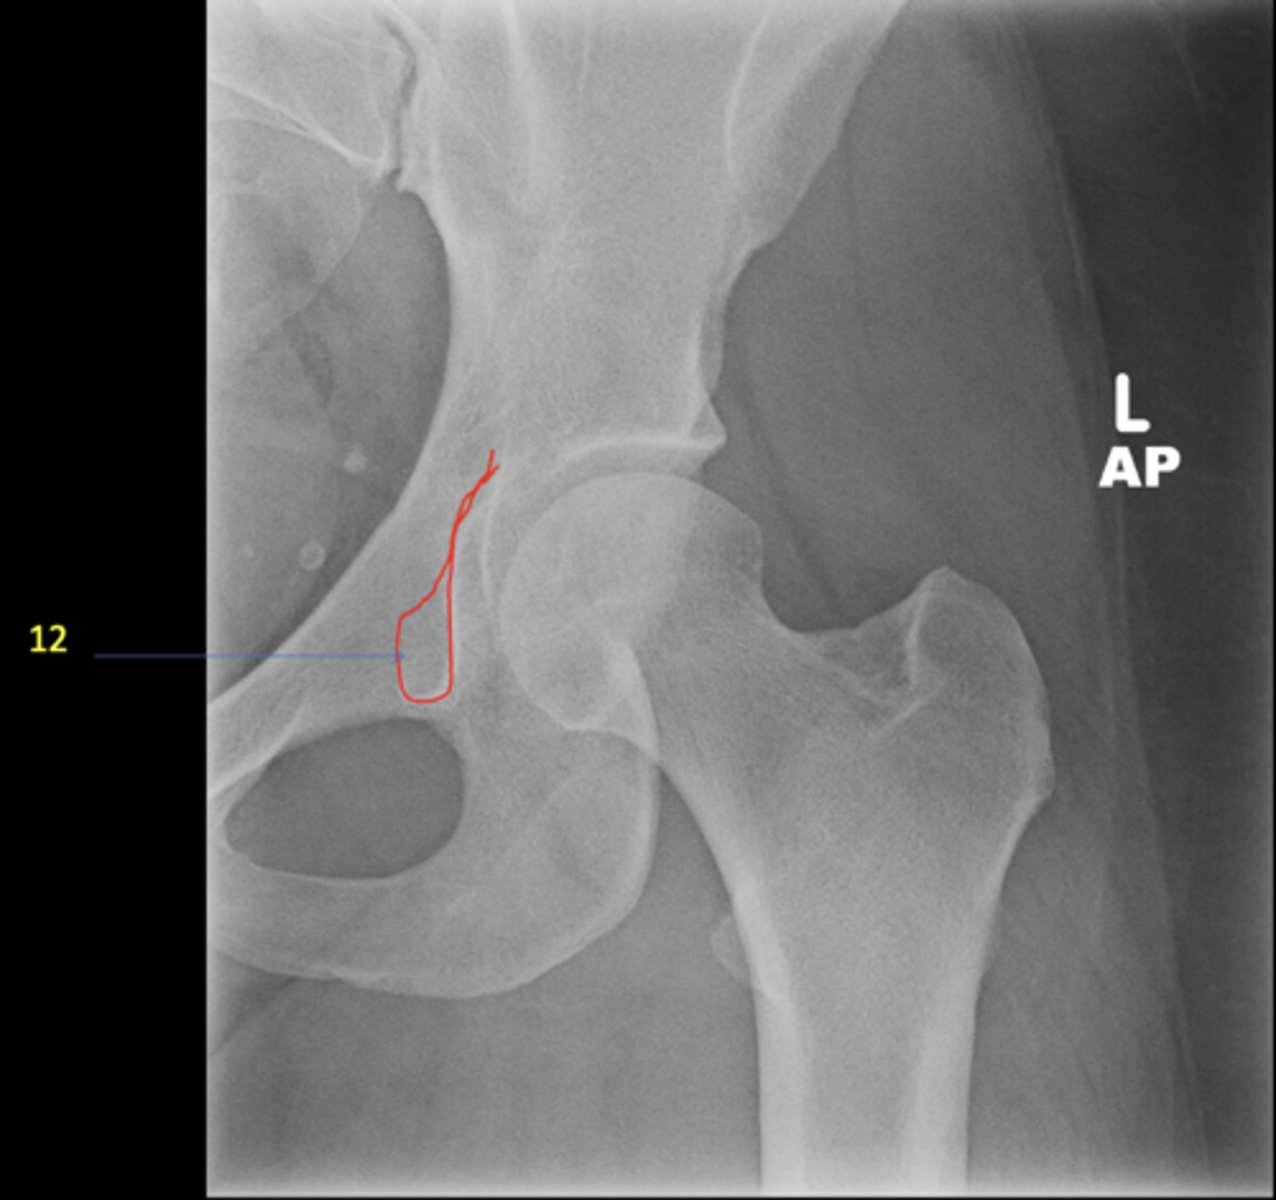

28

New cards

Left AP hip

View?

29

Phleboliths

ID 1

31

Kohler's teardrop

ID 3

Gluteus medius

ID 4

<p>ID 4</p>

33

12

Left femoral neck

ID 12